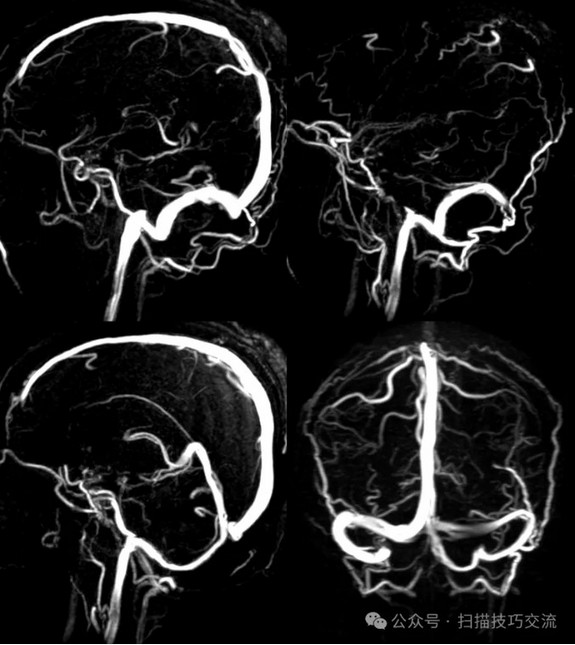

临床申请:颅脑平扫,静脉成像,磁敏感成像,颅内静脉血管黑血成像。

PC-MRV未见异常。